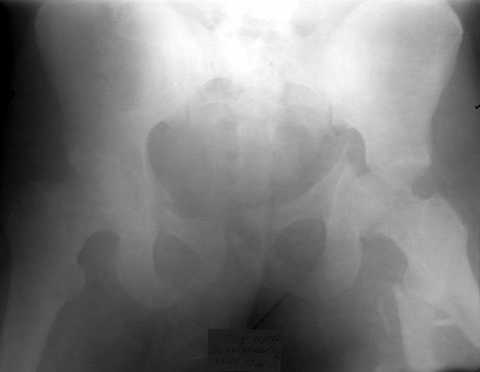

Уважаемые коллеги.Пациент 22 лет поступил 10.08.03. после ДТП. 11.08. жировая эмболия с суточной комой. В настоящее время в сознании, имеются невыраженные психические нарушения. Проводится скелетное вытяжение грузом 13кг.

В плане одномоментное вправление вывиха, наложение АВФ на бедро и скелетное вытяжение по оси и боковое за центральный отломок по оси шейки. Возможны ли варианты лечения в условиях ЦРБ?

Если речь о левом тазобедренном суставе, то это не вывих, а высокий перелом вертлужной впадины, требующий оперативного лечения.

Обсудили с коллегой Рунковым, нашим ведущим специалистом по травме таза и вретлужной впадины - здесь однозначно нужно делать открытый остеосинтез вертлужной впадины. Возможно, и лонного сочленения. Для уточнения положения лонно-седалищного фрагмента надо inlet проекцию.

Если этот фрагмент сильно не развернут, есть шанс на закрытое вправление впадины с помощью резьбового стержня, введенного сквозь нижний полюс головки в медиальную стенку впадины. Но шанс этот не сильно велик, поэтому попытку лучше проводить в условиях, позволяющих тут же перейти к открытому остеосинтезу. Для него, в свою очередь, нужны условия - и хирург с необходимыми навыками, и специальные инструменты и имплантаты.